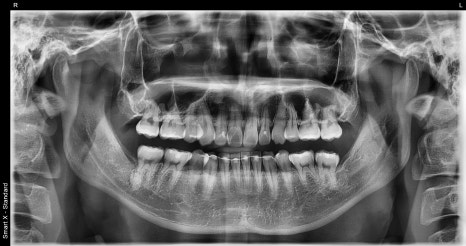

Left photo: An X-ray taken about 10 years after finishing orthodontic treatment, showing the overall tooth alignment and the position where the retainer was attached.